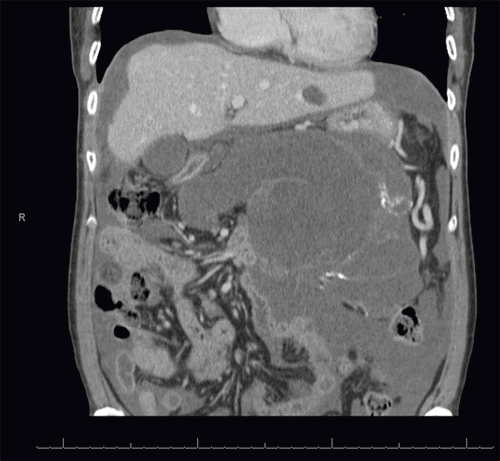

Figure 1. Radiographic Delimitation of Pancreatic Involvement at the Neck. Published with Permission

Axial contrast-enhanced CT of the pancreas. The image demonstrates the interface of the large cystic neoplasm with the more proximal pancreas. A small amount of preserved pancreatic parenchyma is noted at the level of the pancreatic neck, demarcating the proximal extent of the tumor’s involvement

A 54-year-old woman with a past medical history of hyperlipidemia and hypothyroidism presented to an outside hospital to evaluate vague symptoms of abdominal pain, bloating, and weight loss for several months. Her initial workup revealed significantly elevated tumor markers: CA 19-9 at 1834 U/mL, CEA at 10.8 ng/mL, and CA 125 at 64.9 U/mL. Computed tomography (CT) of the abdomen and pelvis demonstrated a large 17.7 × 11.2 × 15 cm multiloculated cystic neoplasm with multiple enhancing septations, appearing to replace the pancreatic parenchyma distal to the pancreatic neck. A subsequent positron emission tomography (PET) scan characterized the large pancreatic mass as ametabolic, but noted diffuse fluorodeoxyglucose (FDG) activity within the nodular mesentery.